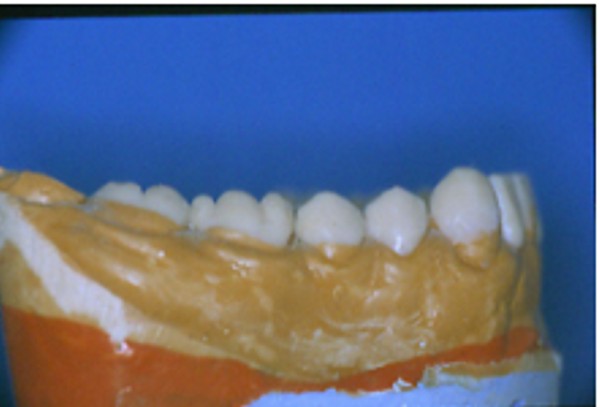

Primera Parte RESUMEN: La alta complejidad inherente a los procedimientos de Rehabilitación Oral, obligan al profesional que la ejerce a basarse en parámetros multidisciplinarios, a veces lo suficientemente intrincados que hacen imposible la práctica de la misma, sin la presencia en su mente de una clara concepción de la Oclusión. The extreme complexity of Oral Procedures, make it imperative for the working professional to rest on multidisciplinary parameters, sometimes so complex that make impossible its practice without the presence of a clear idea of Oclusion. DESARROLLO Suele ser sumamente árido el abordaje de un tema como Oclusión, desde la perspectiva de nuestro diario trabajo ,con todo el strees que este conlleva, con toda la lucha que significan citas, honorarios, diferentes personalidades de los pacientes, inquietudes de los mismos, etc. «LA MEJOR OCLUSIÓN ES LA QUE TIENE LA MEJOR DESOCLUSIÓN» Básicamente, podemos como desde hace ya muchos años se viene haciendo; clasificarlos en: A)Determinantes Posteriores (fijos) Más contemporáneamente, en: I-Mecanismos Primarios: A.T.M. GUIA ANTERIOR INCLINACIÓN DEL PLANO OCLUSAL CURVA SAGITAL DE SPEE FORMA DE LA ARCADA III-Mecanismos Elementales CRESTAS TRIANGULARES INTERNAS Analicemos cada uno de ellos: Es evidente, que la reproducción de las características de la A.T.M., en nuestro aliado fundamental, el Articulador; es imprescindible. Partiendo de la premisa de obtener una OCLUSIÓN MUTUAMENTE PROTEGIDA, para luego arribar al concepto de OCLUSIÓN MUTUAMENTE COMPARTIDA, concepto este que desarrollaremos durante el transcurso de las distintas entregas, analizaremos cada uno de los FACTORES DETERMINANTES DE LA OCLUSIÓN. El primero de ellos, por ser fijo e invariable, solo diremos que: son sus INCLINACIONES PLANARES, o sea : A-INCLINACIÓN DE LA TRAYECTORIA CONDILEA C-BENNET INMEDIATO articuladores totalmente ajustables) D-DISTANCIA INTERCONDILAR. En cuanto a la GUÍA ANTERIOR, mecanismo primario y por supuesto anterior, provee al cuerpo mandibular; del camino a recorrer durante las excursiones protrusivas y lateralidades, a través del vínculo entre las piezas dentarias anteriores, superiores e inferiores. En un corte sagital, podemos observar la relación entre estos donde vemos que se vinculan sin entrar en un contacto franco, sino más bien en una relación de vencindad muy intima a la que llamamos: PUNTO DE ACOPLAMIENTO. Otros factores fundamentales de la GUÍA ANTERIOR son : A-ALTURA FUNCIONAL B-PUNTO DE ACOPLAMIENTO En cuanto a los SURCOS, sabemos que durante una Transtrusión, las cúspides fundamentales generan surcos sobre las piezas que antagonizan. Dichos surcos proveen de una vía de escape a las cúspides antagonistas para evitar colisiones, con las indeseables fuerzas laterales cuya gravedad ya conocemos. MECANISMOS SECUNDARIOS La CURVA FRONTAL DE WILSON, se observa invertida a nivel de los caninos y de los primeros premolares. El PLANO OCLUSAL, en realidad no es ningún plano, sino la sumatoria de muchos MICROPLANOS, los cuales individualmente pueden constituir factores presentes en la OCLUSIÓN, pero auténticos problemas para la DISCLUSIÓN. La CURVA SAGITAL DE SPEE, denominada originariamente de BALKWIL-SPEE, fue concebida como una curva. El cuarto factor SECUNDARIO: el ANCHO DE LA ARCADA, es evidente que variando los ejes de rotación , alrededor de las diferentes distancias ;cambiará la dirección de los escapes (surcos), de los elementos que en el se muevan (cúspides). MECANISMOS ELEMENTALES Los CUATRO NIVELES DE OCLUSIÓN y las CRESTAS TRIANGULARES INTERNAS, constituyen de por si, la herramienta ejecutora de las funciones gnáticas. A- ELEVACIONES 1-Puntas Cuspídeas B-DEPRESIONES 1-Fosas SURCOS DE DESARROLLO De las CRESTAS TRIANGULARES INTERNAS, acentuamos su importancia en ellas dado que son las efectoras finales de la molienda, y su triangularidad debe tener su base partiendo del surco y su vértice terminando en la Punta Cuspídea, condición importante para evitar colisiones durante la transtrusión (movimiento de lateralidad ). EFECTOS DE LA VARIABILIDAD DE LOS FACTORES DETERMINANTES DE LA OCLUSÍON Cada uno de los determinantes influye aumentando o disminuyendo tanto la DESOCLUSIÓN como la ALTURA CUSPÍDEA INCLINACIÓN DE LA TRAYECTORIA SAGITAL INCLINACIÓN DEL PLANO OCLUSAL RADIO DE CURVATURA DE LA ÁNGULO DE LA TRAYECTORIA ALTURA DEL PUNTO DE LATERO SURTRUSIÓN / MOV. DE BENNET INMEDIATO CURVA FRONTAL DE WILSON SURCOS BIBLIOGRAFÍA Dibujos y esquemas tomados del libro: Oclusión Orgánica…un camino hacia la Rehabilitación Oral. 1)William Mc Horris,B.S.,D.D.S. Oclusión. Con especial énfasis sobre :El rol funcional y parafuncional de los dientes anteriores. 2)Von Spee , Craff(Anatomista alemán, describió la curva de compensación de la articulación de molares y premolares).CURVA DE SPEE 1.89 3)Stuart,D.»Some aspects of the inervation teeth.»Procedings of Royal Society of Medicine.20:1675,19274)Muhleman,H. y Savdir,S»Tooth movility-its causes and significance»Journal of Periodontology ,36:153,Marzo ,Abril,1965. 4)Muhleman,H. Y Savdir,S»Toothmovility its causes and significance» Journal of Periodontology,36:153,marzo,abril,1965. 5-Oclusión y Diagnóstico en Rehabilitación Oral. 6-Anatomia Odontológica. -A contribution to the study of the movementes of the mandible. 8-Celenza F.W, Nadeskin J.F.,Oclusión.Situación actual. 9-D´Amico 10-Dawson P.E. 11-Huffman -Regenos. 12-Hobo S.-Takayama H.A. 13-Lucia V.O 14-Mc Horris. 15-Mc Horris. 13-Posselt U. 16-Stuart C. 17-Vartan Veshnilian

Efectuado de esta manera un somero análisis de los principales factores que determinan la OCLUSIÓN, hemos de plasmar en un caso clínico de alta complejidad; todos los conceptos aquí vertidos mostrando a la OCLUSIÓN ORGÁNICA como un camino práctico y real que nos lleva a la concepción y concreción de la REHABILITACIÓN ORAL INTEGRAL.